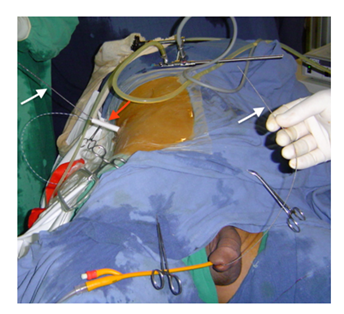

All procedures were carried out under general anesthesia. The patient was placed in the modified supine position. The flank is elevated 30 to 45° with regard to horizontal plane and lower limbs are split and bent in a lower position (Figure 1). The retrograde approach was used initially in all cases. If unsuccessful (Failure to find ureteric orifice or Failure to cross stricture), antegrade or both antegrade and retrograde approach was attempted. The most accessible posterior calyx was punctured under ultrasound guidance using a 22G Chiba needle and the tract dilated to 10 Fr. Radiopaque contrast and Methylene blue were injected into the renal cavity. The renal pelvis, Pelviureteric junction and calyces were identified as the seat and length of the stricture (Figures 2A & 2B). Once the pelviureteric junction was crossed and the ureter accessed, a straight hydrophilic guide wire and a special intrarenal manipulation catheter were used to cross the malignant ureteric stricture (Figure 3). If the stenosis was too tight and that the guide failed to pass, a resection guided with fluoroscopy in the direction of the guide was performed in the same flank modified position. The resection was continued until visualization of the guide and Methylene blue.

Figure 1 Modified supine position: The flank is elevated 30 to 45° with regard to horizontal plane and lower limbs are split and bent in a lower position.

The wire was then advanced into the bladder and preferably harbored with an extracting forceps. This guide wire was then exchanged for an ultra-stiff guide wire. The end of the guide-wire is secured with a clamp at the skin level and the desired steerable stent is positioned under radiographic control in a retrograde fashion over the harbored tip of the guide-wire. Finally, the wire is extracted through the puncture and the stent is released in its correct position. In some cases, dilatation of the ureteric stricture was performed. We used for this purpose an Amplatz sheath, through which progressive increasing size ureteral stents were passed. Applying some tension on the extremities of the guide wire facilitates this maneuver (Figure 4). A final fluoroscopic image was stored to document the stent position. An 8 Frnephrostomy drainage catheter was placed and removed in 48-hours following a satisfactory nephrostogram.

Figure 4 Dilatation of the ureteric stricture through an Amplatz Sheath (red arrow): note the guide wire is introduced though the renal access and extracted through the urethral meatus (white arrows).